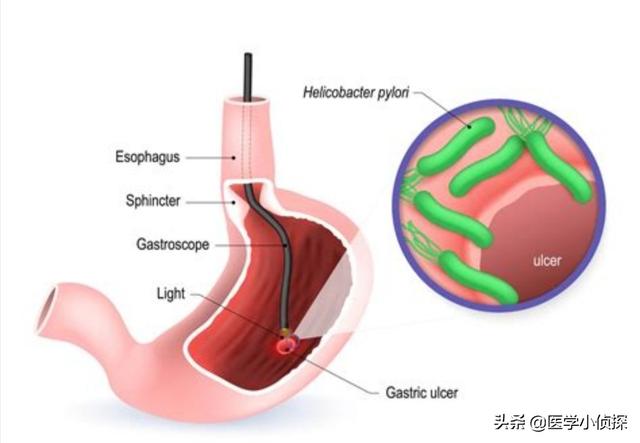

第一に、感染症について触れなければならない。そして最も注目すべきは、世界保健機関(WHO)が明らかにしていることだ。ヘリコバクター・ピロリ感染は胃癌の発生と強く関連しているピロリ菌に感染した初期のように、急性の炎症が起こり、その後、どんどん長い期間をかけて胃に慢性的な炎症性変化を引き起こし、前がん病変につながる可能性がある。そのため、1994年に世界保健機関(WHO)の国際がん研究機関(IARC)によって、ピロリ菌感染は発がん性物質群として定義された。もちろん、ピロリ菌以外にもEBVなどの感染因子がある。

まず感染因子だが、ピロリ菌の相互感染が考えられる!ヘリコバクター・ピロリの感染は人から人へであり、人が唯一の感染源である。この種の感染は、口から口へ、口から口へ、糞便から口へであり、非常に広がりやすい。たとえ一緒に食事をしたとしても、共用の箸を使わなければ、夫婦のどちらかがヘリコバクター・ピロリに感染していることになり、もう一方も非常に感染しやすい。そして、最終的に除菌に成功したとしても、再感染しやすい。

もちろん、ヘリコバクター・ピロリ菌に感染したからといって、必ず胃がんになるわけではなく、そのほとんどに罹患はないが、長期にわたるヘリコバクター・ピロリ菌の感染は、慢性胃炎、消化性潰瘍、胃がんなどの一連の臨床疾患を引き起こす可能性が高く、リンパ腫などもこのヘリコバクター・ピロリ菌の感染と明らかに関連しており、ヘリコバクター・ピロリ菌の感染も発がん物質の一種として論文で言及されている;

お招きありがとうございます!胃がんの原因には、胃ポリープ、萎縮性胃炎、ピロリ菌感染、長期高塩分食、長期漬物食、遺伝などいろいろあります。しかし、夫婦同時に胃がんが発覚する最も可能性の高い理由は、胃がんになりやすいピロリ菌に二人とも感染していること(同じ茶碗、箸、キスなど)である。ピロリ菌は強力な胃酸の中で生存・繁殖できる唯一の細菌で、発がん性細菌の一種として、中国人の感染率は約60%、慢性胃炎の多くはピロリ菌の感染が関係している。中国医科大学によると、ピロリ菌に感染している人の少なくとも1%が癌化するという。現在、検査は特に簡単で、病院で息を吹きかければ(違和感なく)陰性か陽性かがわかる。治療は複雑ではない。西洋医学では、オメプラゾール(またはランソプラゾール)+コロイド状ビスマスペクチン+アモキシシリンカプセル+メトロニダゾール、プロバイオティクス、漢方薬では梅干(おやつとして食べられる)。14日間服用し、夫婦で同時に治療する。効果は非常に良い。

以下はヘリコバクター・ピロリの図である。